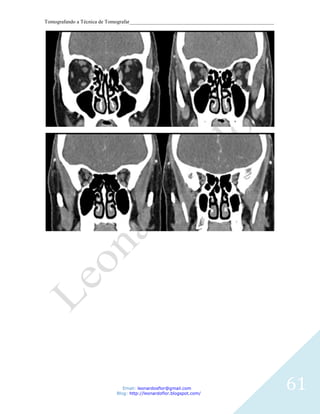

SPN

Cortes Coronais – Prono e Supino

TÉCNICA DE EXAME

Perpendicular ao palato duro.

Início na parede posterior do seio maxilar e término na margem anterior do seio frontal.

3 mm de espessura.

3 mm de intervalo.

Filtro para partes moles/ósseas.

Uso de contraste depende da indicação clínica.